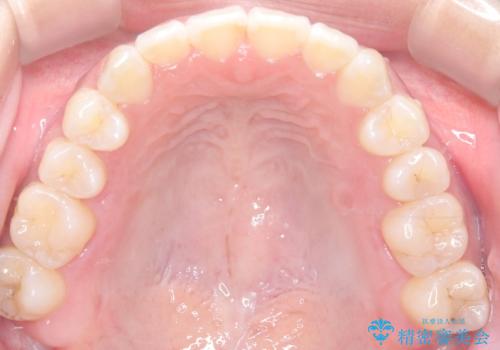

- 治療計画

治療では、審美ワイヤーを使用し、目立ちにくく配慮しながら矯正を進めました。上顎にリンガルアーチと矯正用アンカースクリューを用いて臼歯部を安定的に遠心移動させ、歯列全体のスペースを確保しました。その後、回転していた前歯を正しい位置に配列し、全体的な歯並びの改善を行いました。治療中は、装置の適切な管理と口腔衛生を徹底することが重要でした。結果として、見た目だけでなく機能的にも優れた歯列を実現することができ、患者様にもご満足いただけました。